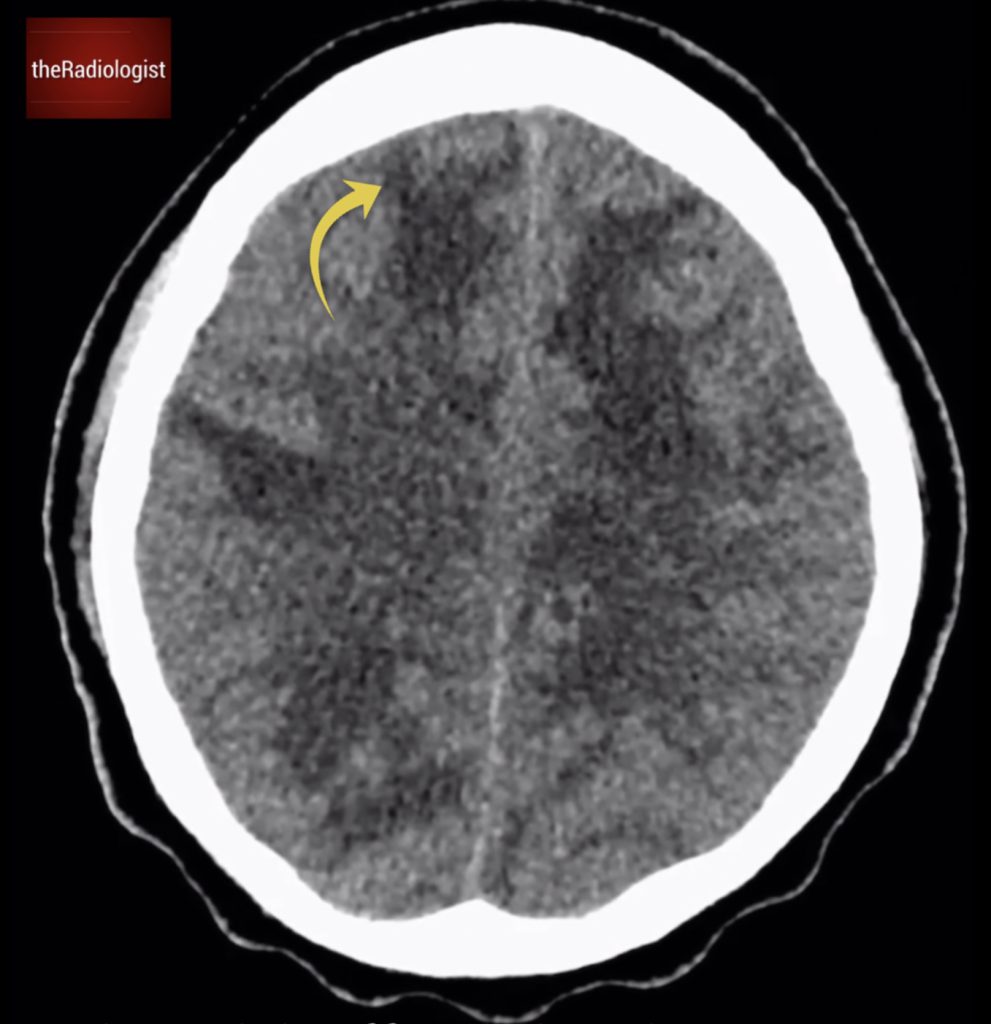

Single axial slice of a non contrast CT head.

Let’s take a closer look at this brain CT scan. Looking carefully we will find multiple foci of low density scattered throughout the brain. These areas exhibit finger-like projections extending to the edge of the brain, a classic pattern indicative of white matter involvement. This finding strongly suggests vasogenic oedema: when you see this you need to consider an underlying space-occupying lesion.

Low density with finger-like projections extending out to the edge of the brain suggesting white matter involvement and vasogenic oedema.